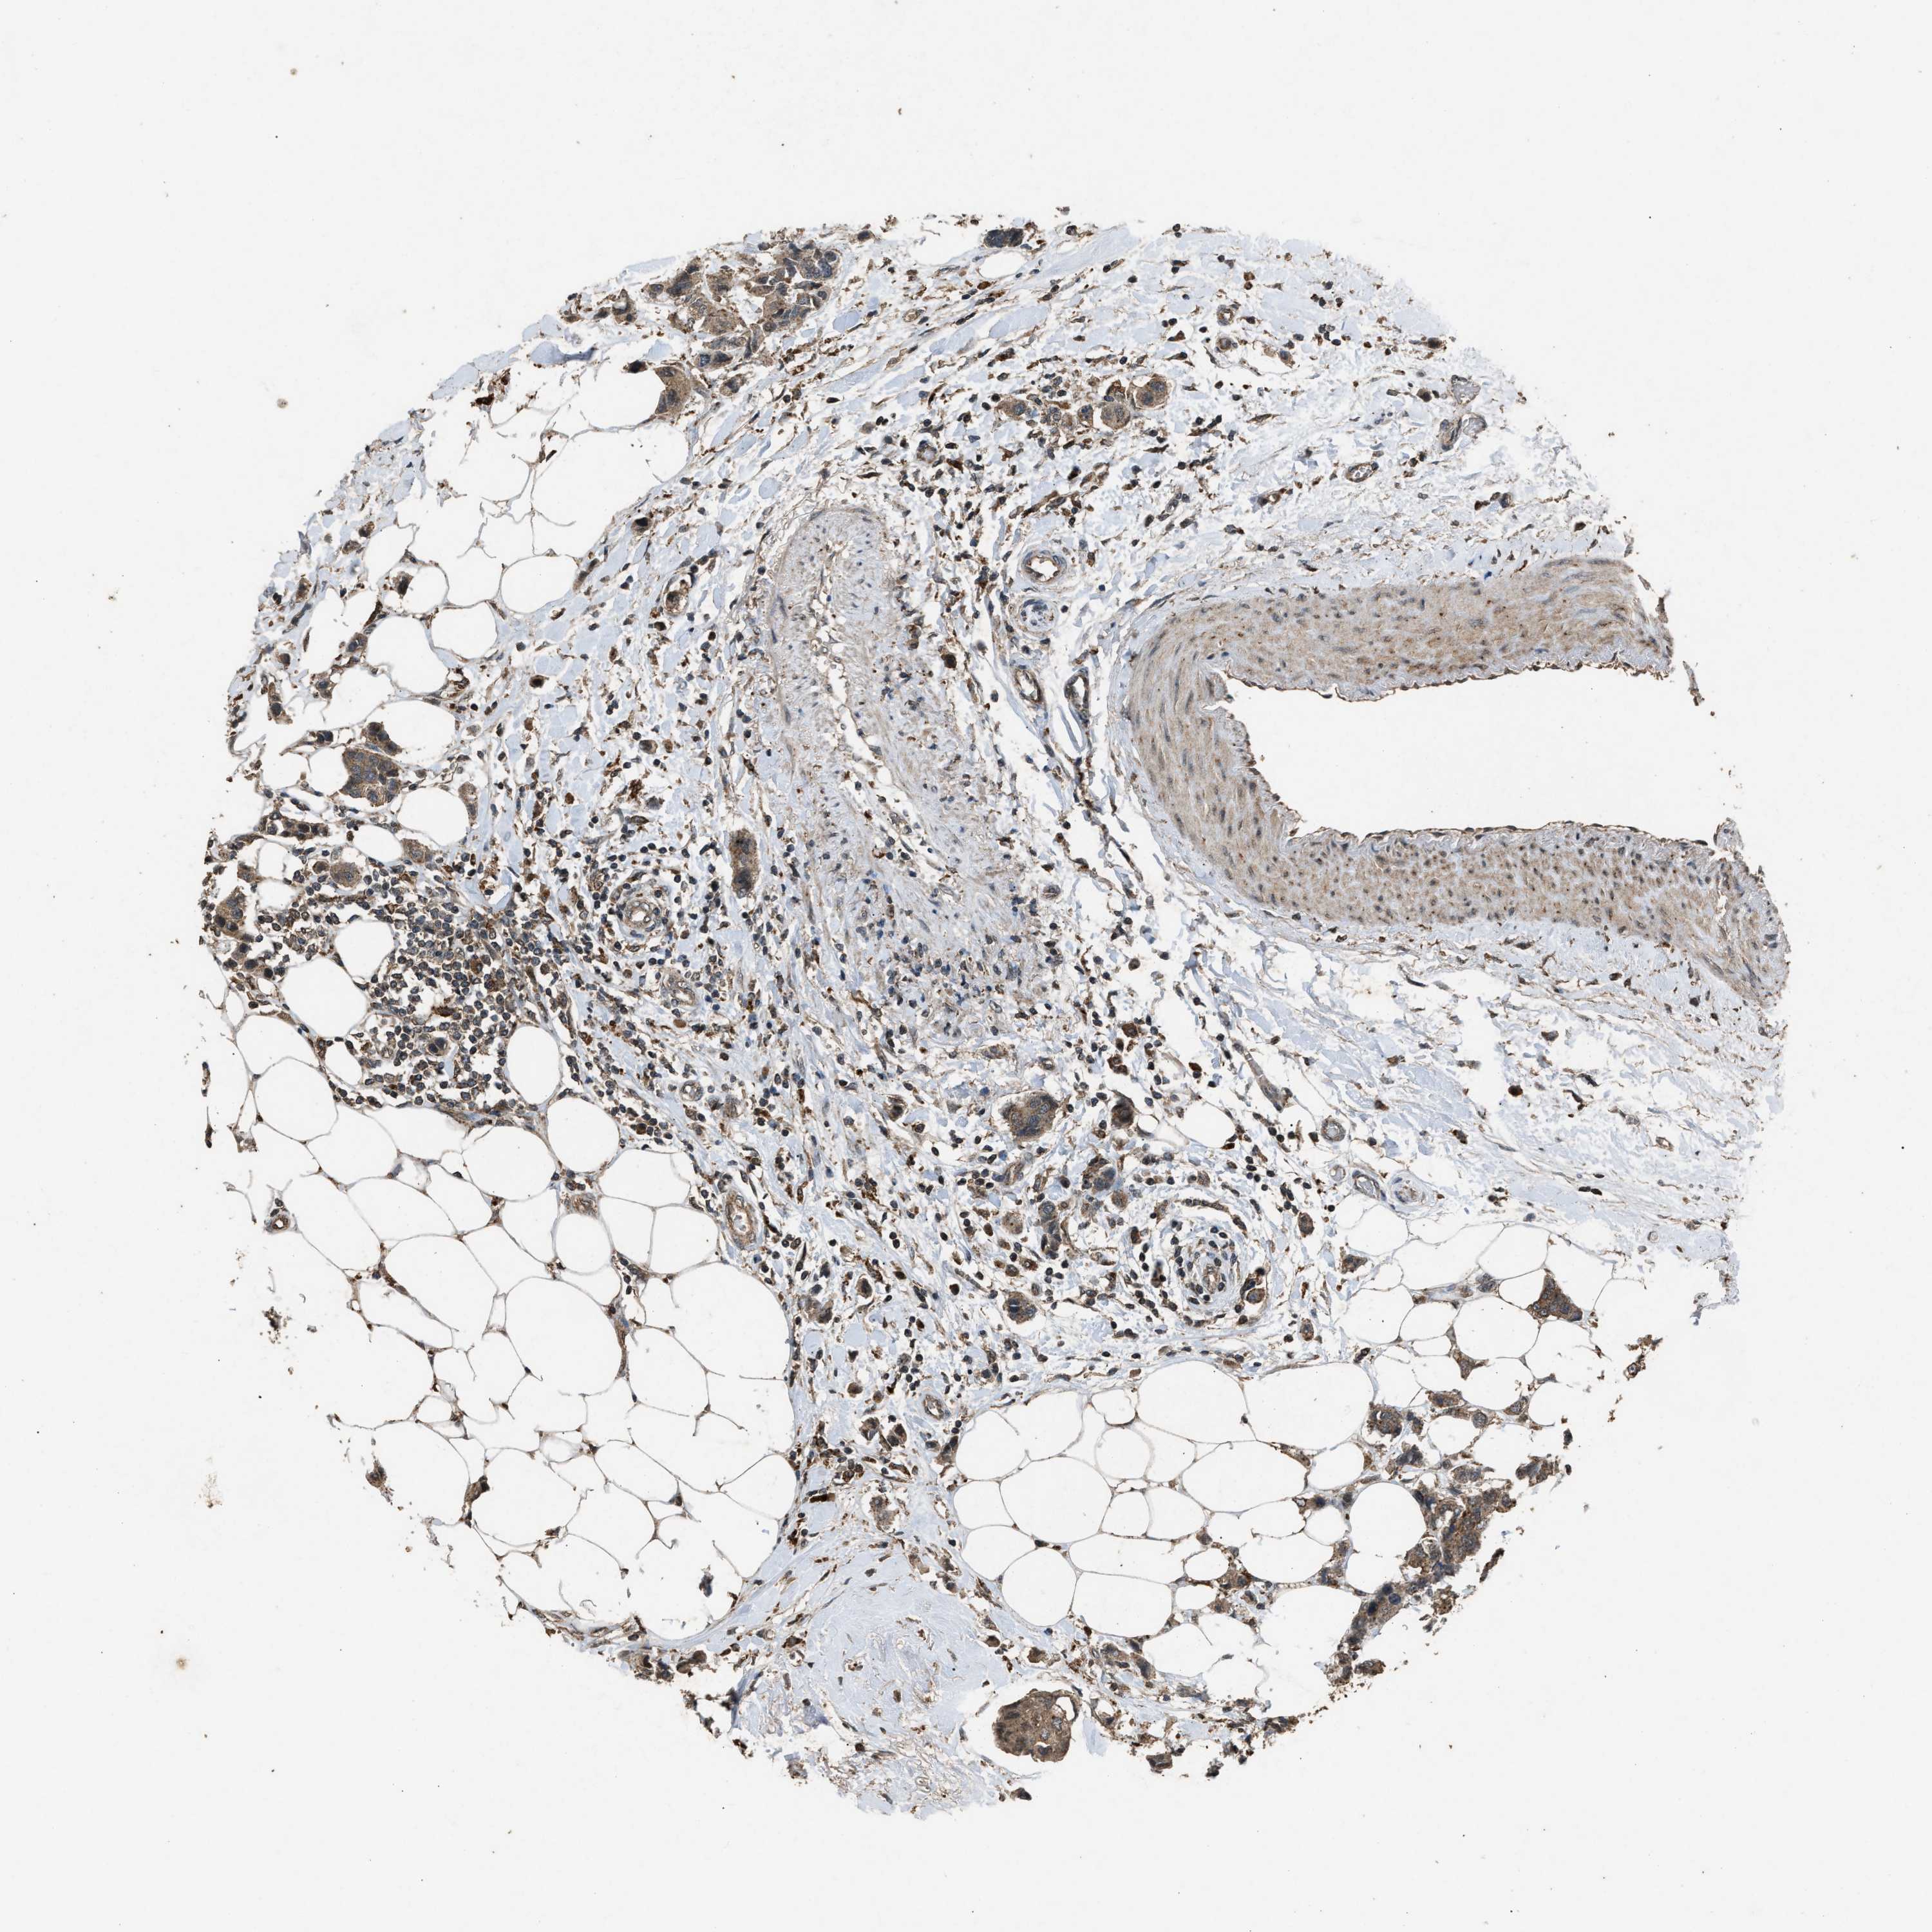

BRCA TCGA BRCA VALIDATION PROTEIN EXPRESSION

ANTIBODIES

AND

VALIDATION